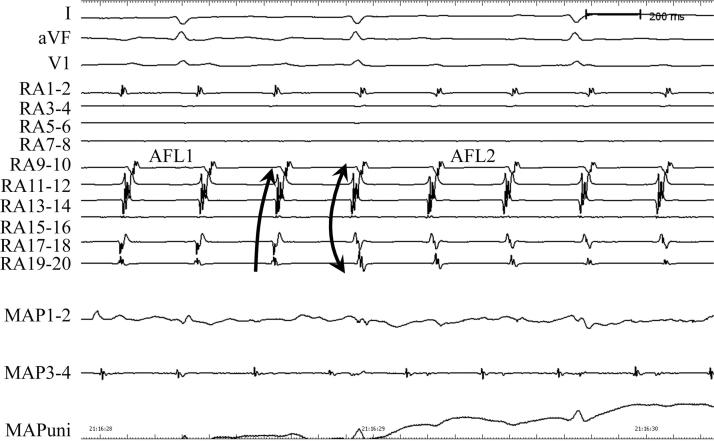

Implantation of ileofemoral stents: A novel approach for bilateral occlusions of the iliofemoral vein in a patient with a Glenn operation.

HeartRhythm Case Rep. 2015 Dec 24;2(2):138-141. doi: 10.1016/j.hrcr.2015.11.010. eCollection 2016 Mar.